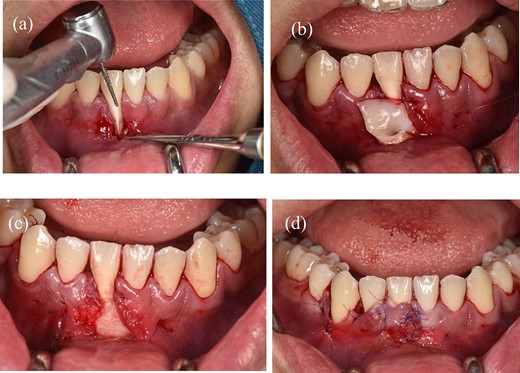

(a) Preparing the tooth surface using a high-speed handpiece. (b) Unilateral tunneling technique. (c) Stabilize the connective tissue graft. (d) Rotate the flap and reposition the gingival margin.